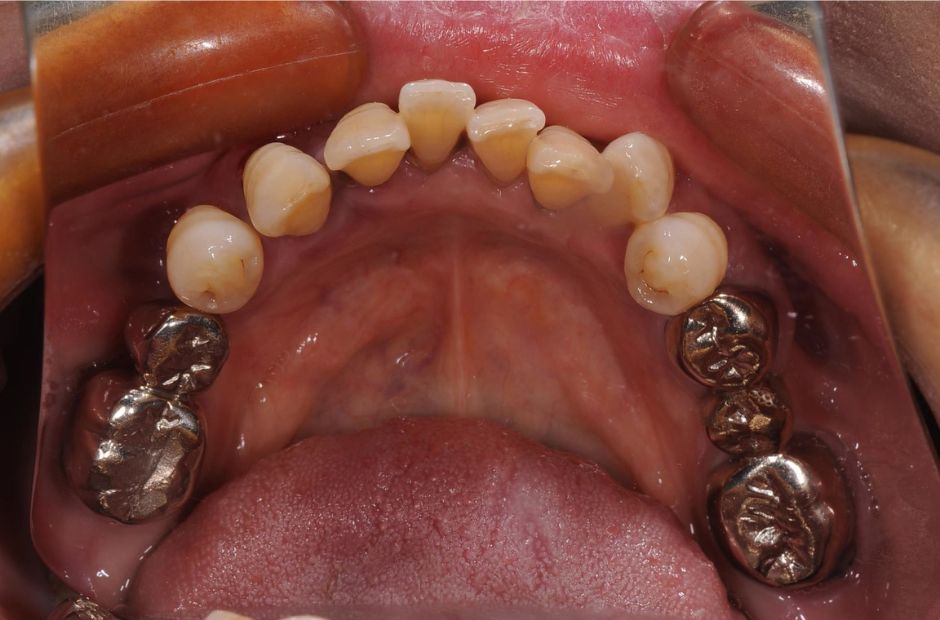

case.02

差し歯とインプラントの治療

若年の患者様が前歯の審美性について相談に来られました。差し歯とインプラントの組み合わせにより、自然で美しい笑顔を実現しました。患者様は見た目の改善と機能性の向上に大変満足されました。